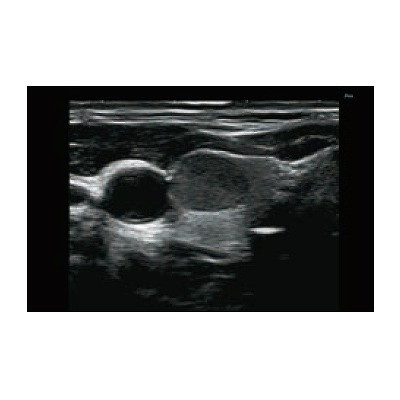

●動脈硬化の評価やシャントにおける機能評価も簡便に